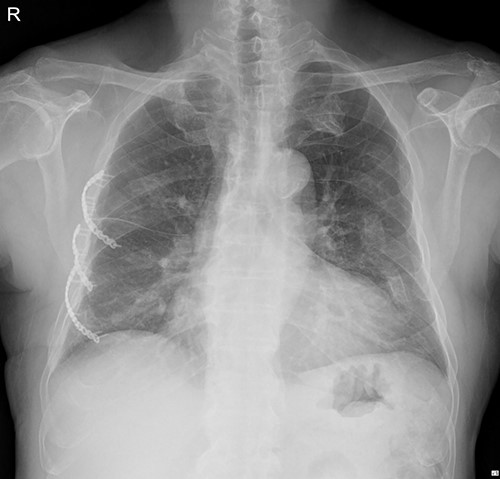

The submuscular emphysema, however, was increased in size, and the patient was eventually re-hospitalized. A small incision was made beneath the surgical wound under local anesthesia, and a 10 FR thoracic drainage catheter was carefully placed into the submuscular layer (Fig. 4.). Under 2 L of oxygen supplement, the submuscular emphysema gradually decreased over several days, and the patient was finally discharged on hospital Day 6 (Fig. 5). Since his last readmission, there have not been any more complications.

Chest X-ray after applying a 10 FR drainage thoracic catheter into the submuscular layer (11 March 2022).